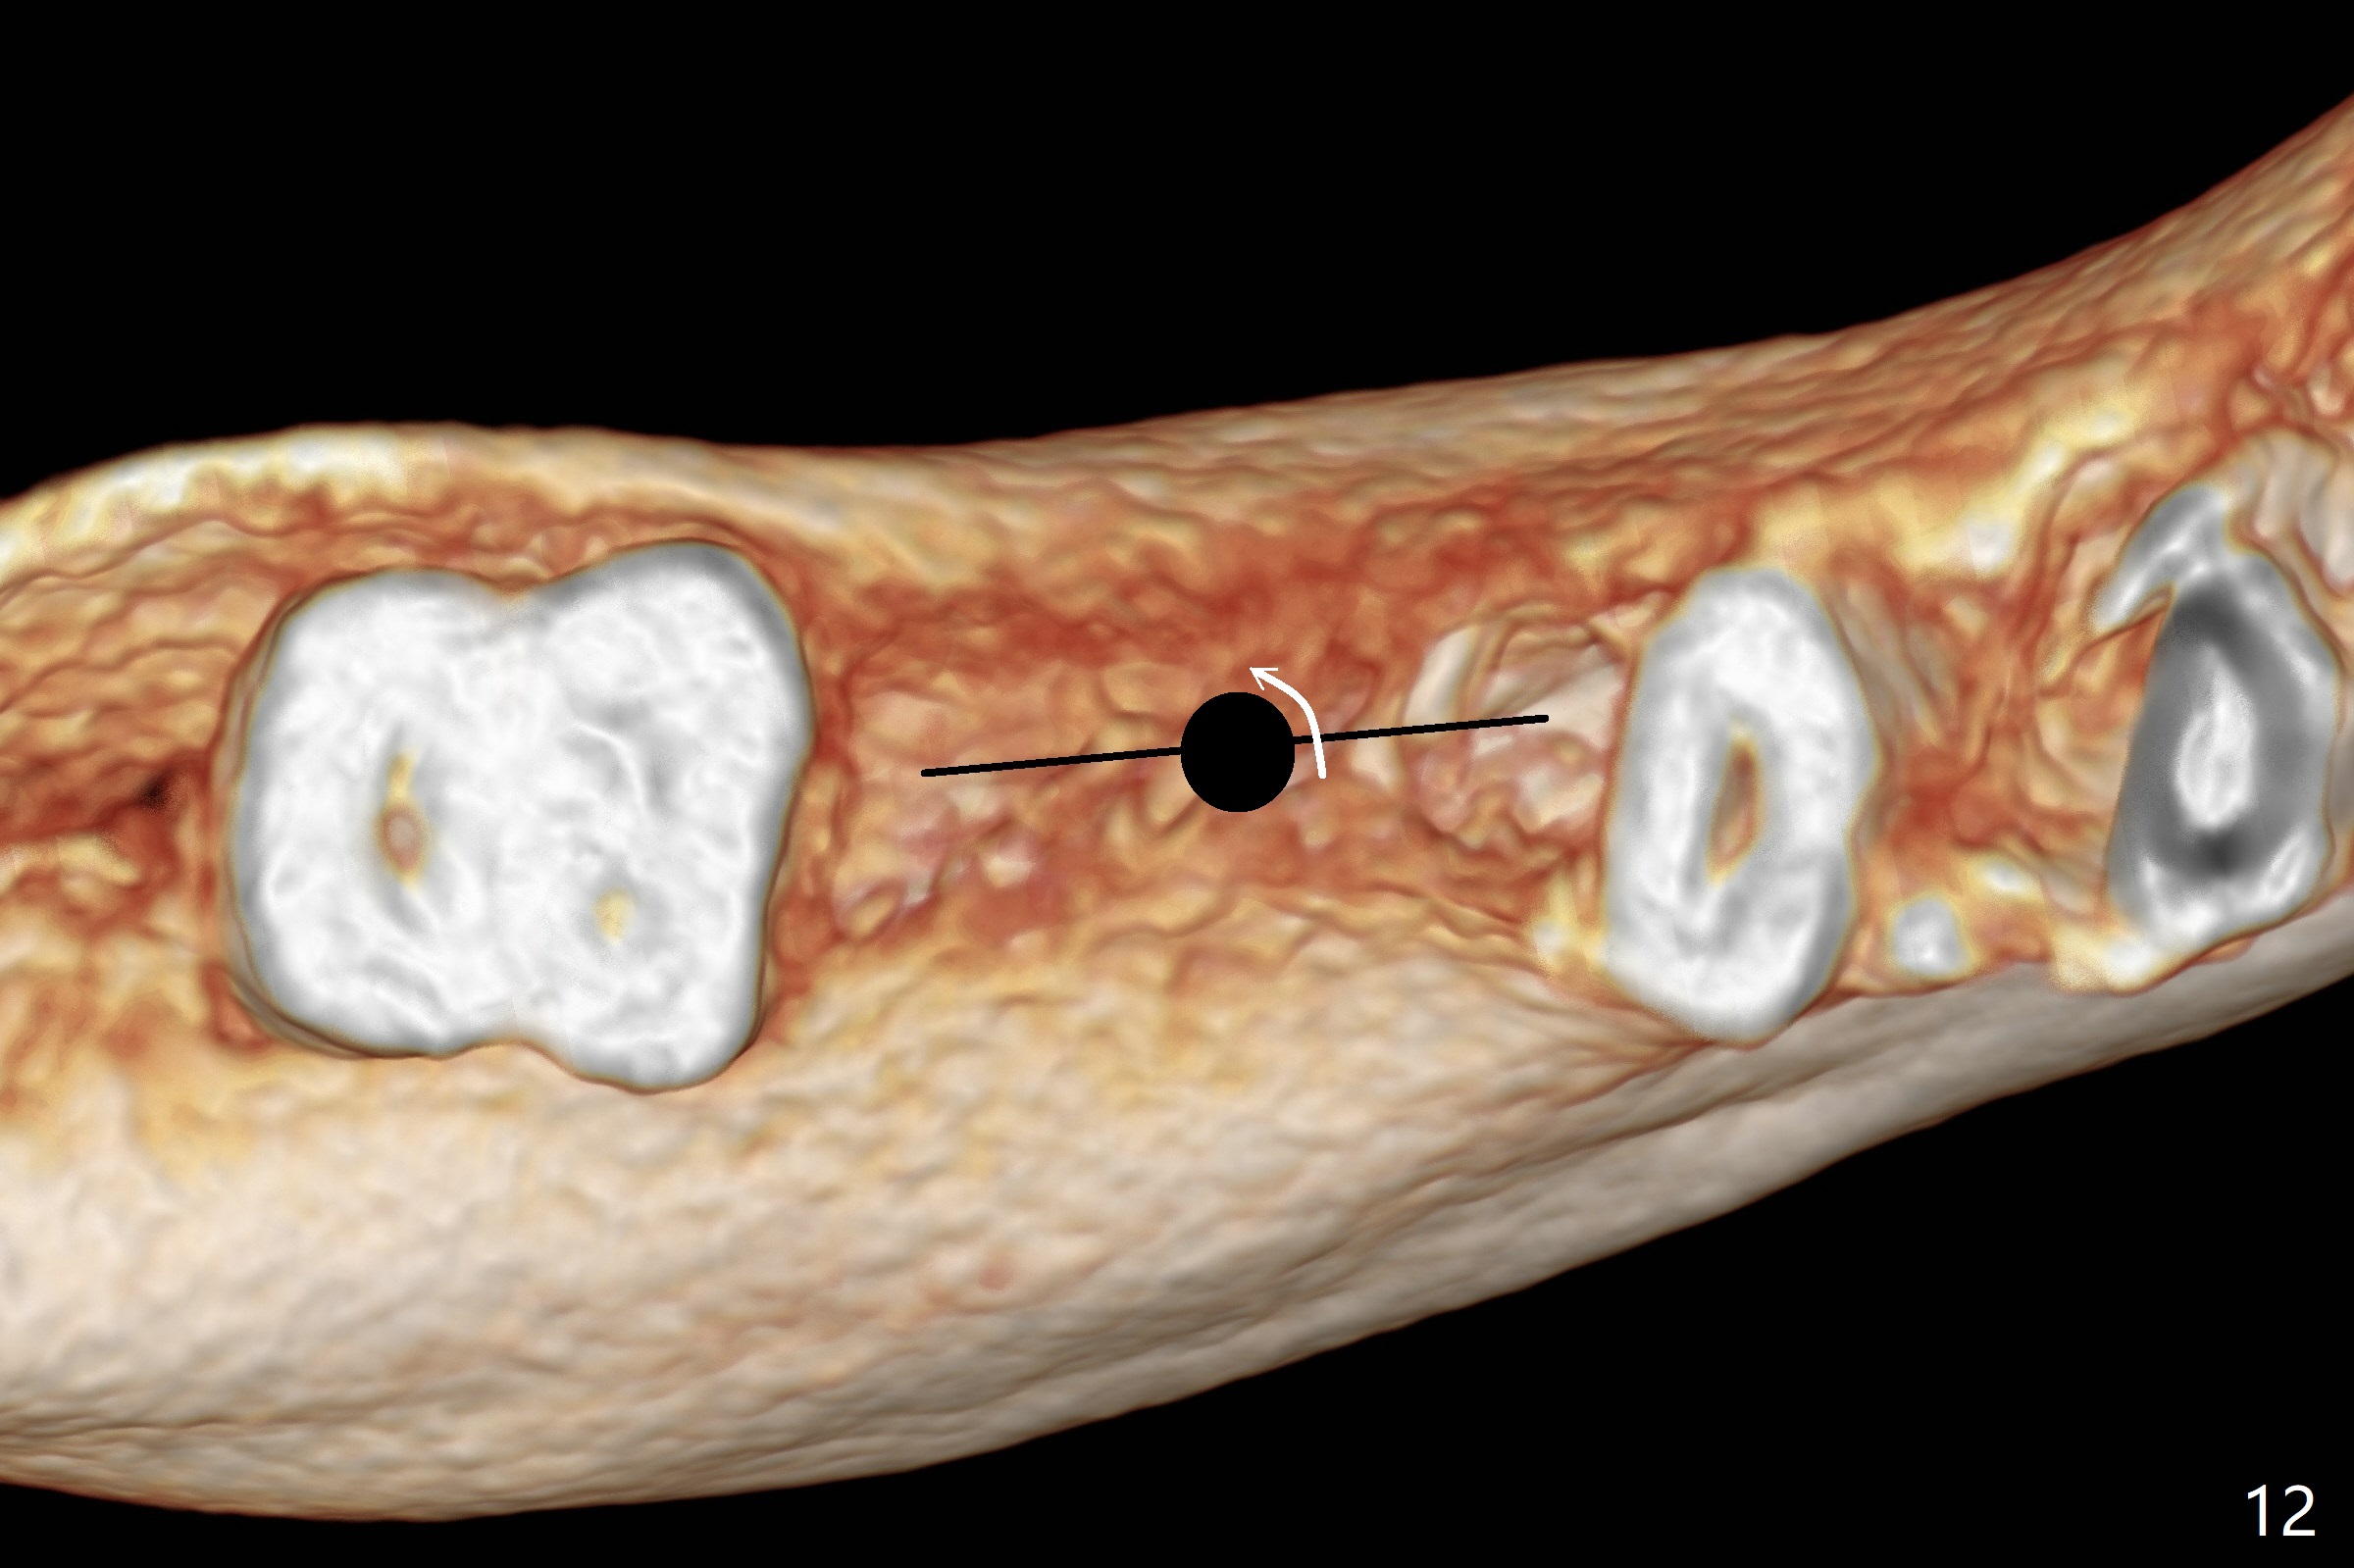

The ridge at #30 is narrow (~ 4 mm buccolingual and ~7 mm mesiodistal, Fig.8). A 4x11.5 mm will be placed. Impression will be taken for guides for #28 and 30. Incision will be made prior to guide seating (Fig.9 occlusal view); initial osteotomy (Fig.10 black circle) will be conducted with guide clockwise (white curved arrow). With removal of the guide, the ridge is split (Fig.11 black line). Osseocondensation drills will be used for ridge expansion with the help of guide (in the middle of the metal sleeve, Fig.12 counterclockwise).